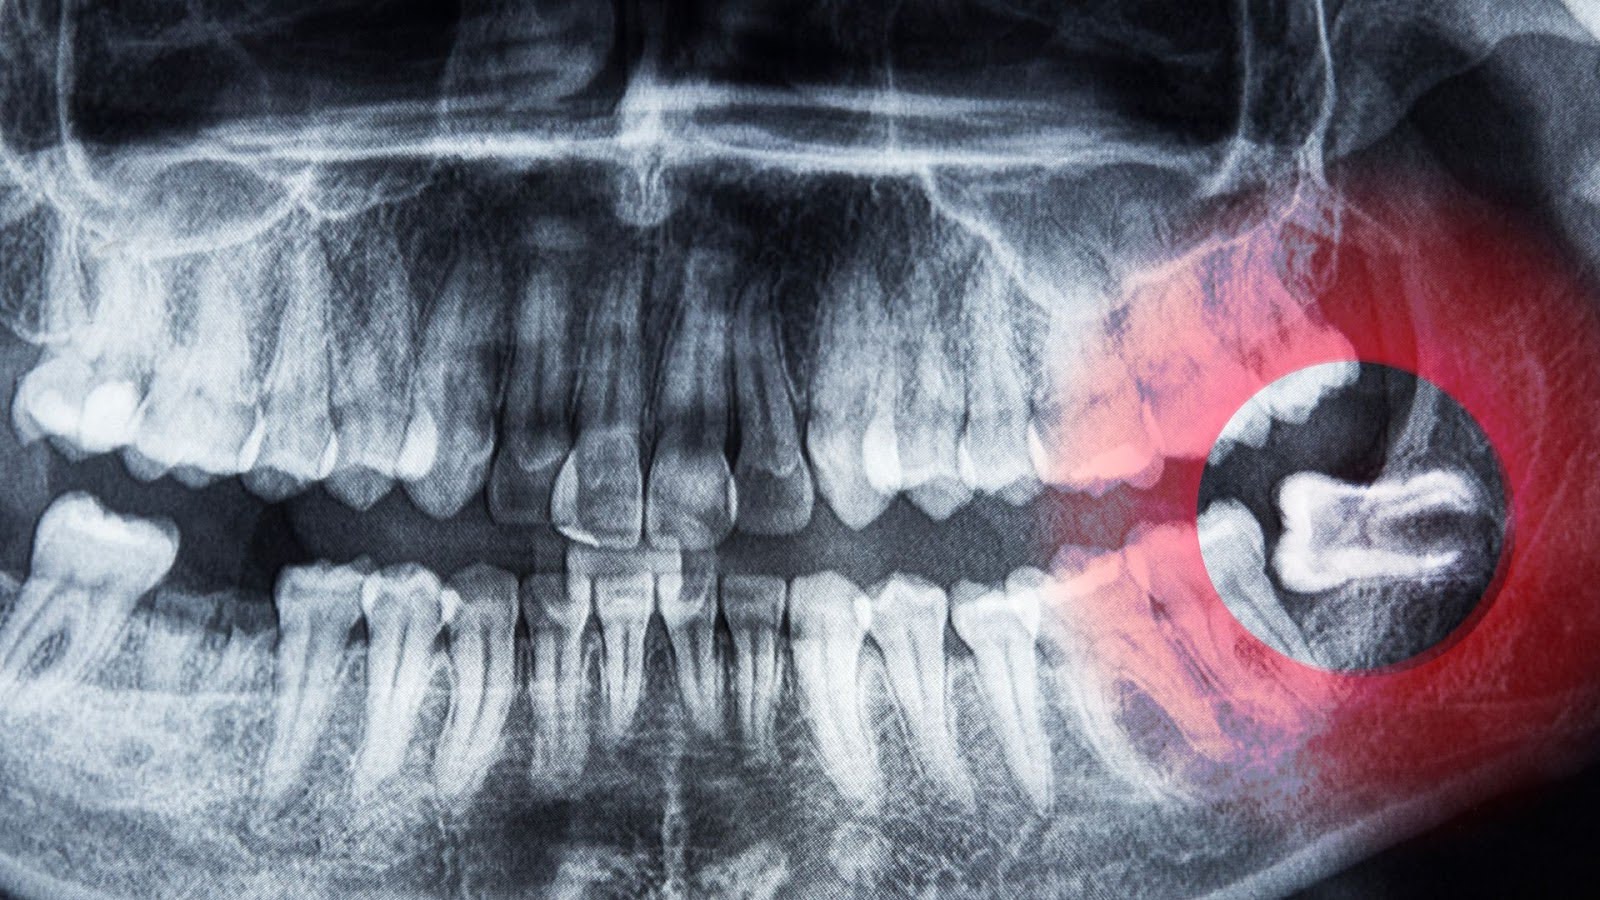

Wisdom teeth are the “third molars” that usually appear in your late teens or early twenties. While some people have plenty of room for them, most of us don’t. When a tooth cannot fully break through the gum, it becomes impacted.

- Technology-Driven Precision: We use X-rays to see exactly where your roots are located. This reduces surgery time and speeds up your healing.